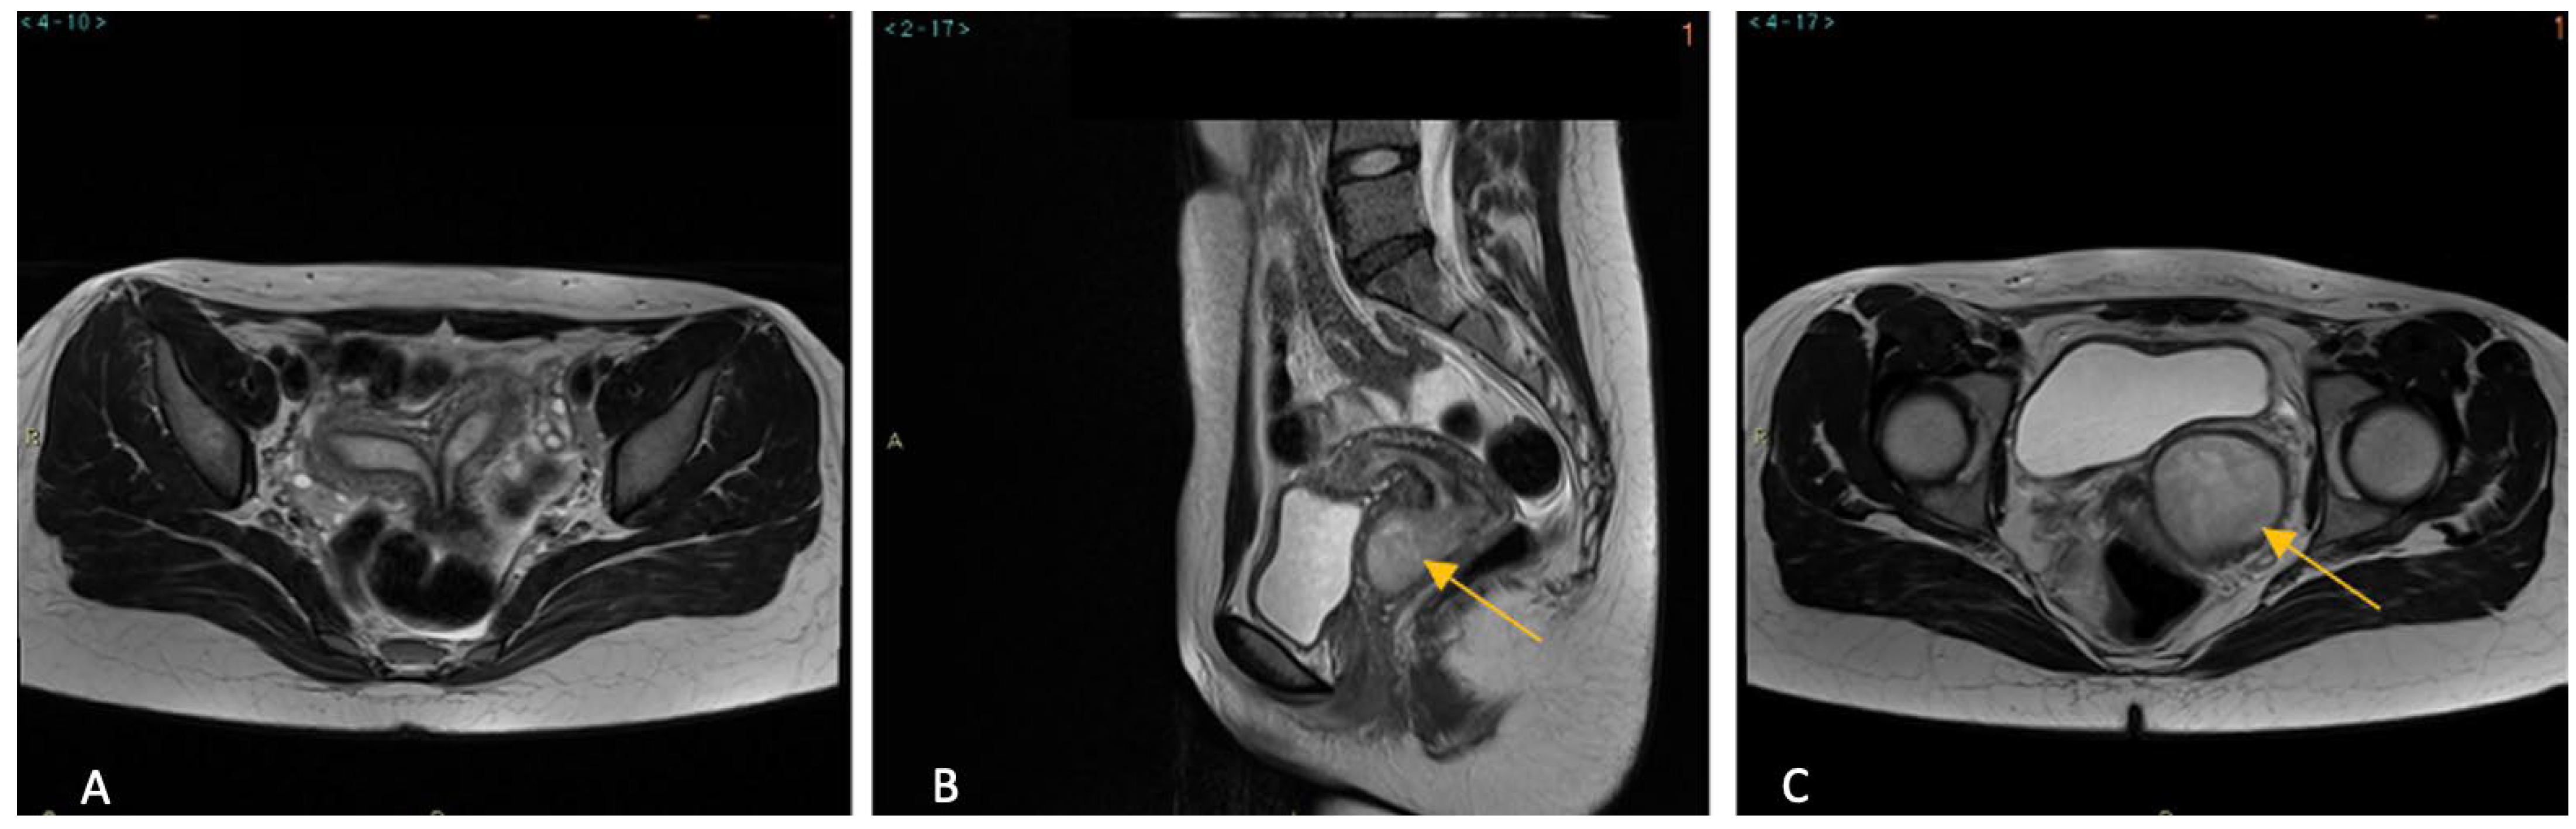

CT scan and MRI confirmed the findings. In addition, MRI clearly demonstrated two vaginal cavities. The right hemivagina was seen to communicate with the right cervix and corresponding uterine horn. Instead, the left hemivagina was markedly distended, suggestive of a left hematocolpos (Figure 1). No evidence of focal implants of endometriosis were detected. All these findings were consistent with obstructed hemivagina and ipsilateral renal anomaly (OHVIRA) syndrome.

Figure 1. MRI images (A), axial T2 weighted image of didelphis uterus. (B) sagittal section of the T2-weighted MRI scan demonstrating didelphys uterus with left hemiuterus and hematocervix. (C), Axial T2 weighted image of the dilated left hemivagina and the presence of hematocervix (arrow).